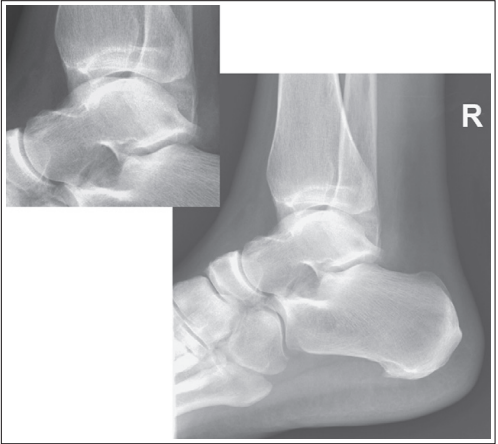

What are the issues with this mortise ankle?

Posterior and anterior tibial margin can be seen

Distal leg is elevated

Medial mortise is closed, and anterior tibial margin has been projected proximal to the posterior margin

Distal tibia has been elevated